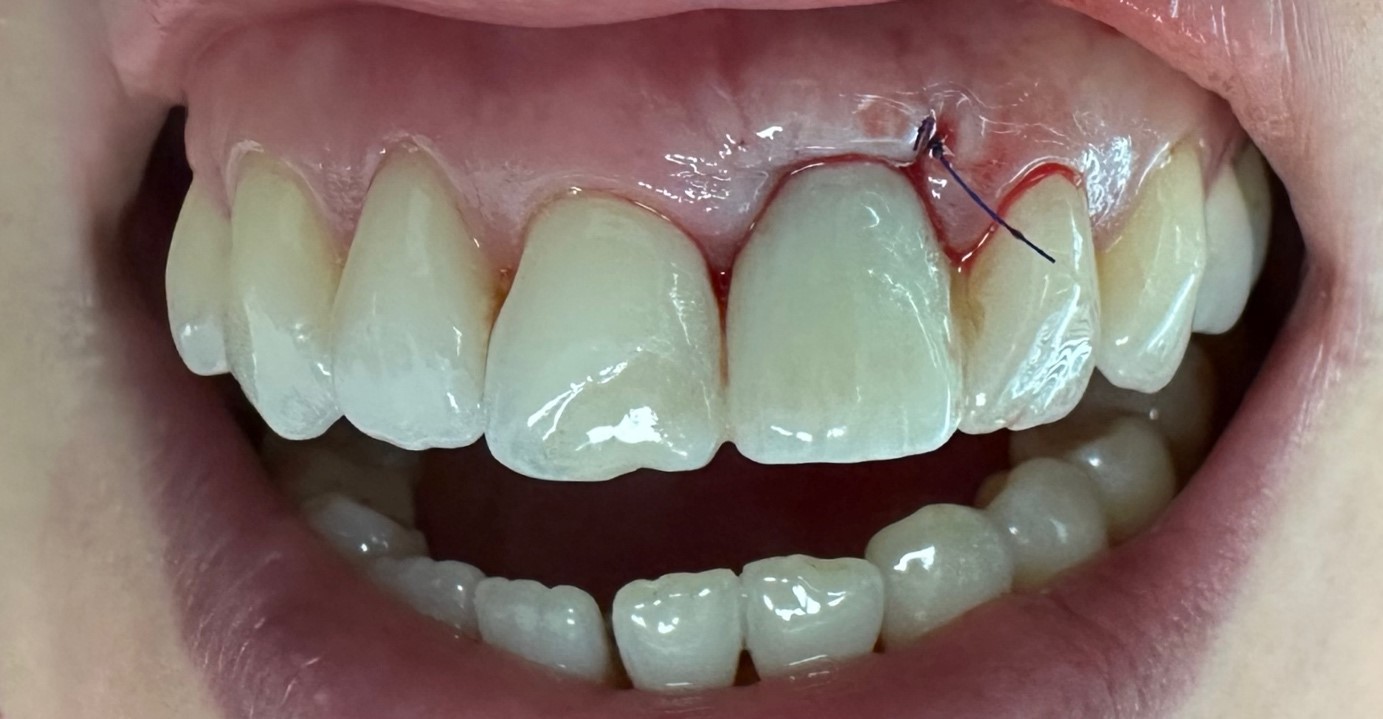

Widok w jamie ustnej po usunięciu zęba (jedynka górna lewa) i wprowadzeniu implantu

Chirurgia: dr n.med. Ewa Zawiślak

Protetyka: dr n.med. Ewa Zawiślak